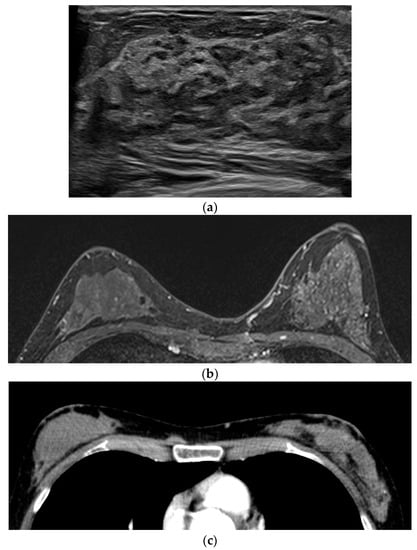

Figure 2. A 42-year-old woman with palpable mass at breast periphery. (a) In the ultrasound, a 2.3 cm irregular hypoechoic mass was detected in the palpable site of the right breast at the 4-o’ clock periphery and confirmed as invasive ductal carcinoma by core needle biopsy. (b) No discernible enhancing lesion at the correlating site in the early phase of dynamic contrast-enhanced T1WI. This palpable mass showed definite diffusion restriction with an ADC value of 0.68 × 10−3 in DWI b = 1000 (c), ADC map (d), and homogeneous enhancement in contrast-enhanced chest CT in the supine position (e).

In four cases (Nos. 6–9), the lesions were located in the breast periphery or chest wall and showed no enhancement; IDC (n = 3), metaplastic carcinoma (n = 1). These lesions were not detected in DCE MR, but all showed definite diffusion restriction, and the measured ADC values ranged from 0.68 to 0.96 × 10−3 mm2/s. Three of these lesions showed distinct homogeneous enhancement on contrast-enhanced chest CT (Nos. 6, 8, and 9) (Figure 2).

The second is by location. During the breast MR examination, the patient lies in a prone position, with the chest hanging freely in the recesses of the coil. This method allows breast tissue to spread and prevents respiratory motion artifacts, ultimately facilitating lesion detection [18]. If the lesion is located on the breast periphery or chest wall, contrast media may not be sufficiently delivered due to this posture [6]. In the four cases, no lesions were found in DCE MR. On the other hand, these lesions demonstrated diffusion limitation and low-range ADC values in DWI independent of the contrast agent [19,20]. Three of these lesions showed homogeneousness or rim enhancement in contrast-enhanced chest CTs performed in the supine position. Although the mechanisms of contrast enhancement in CT and MR are different, this indicates that the location does matter.